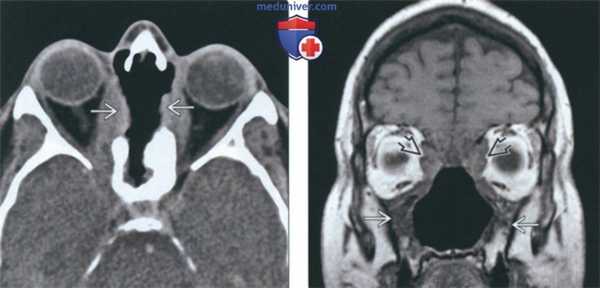

(Слева) На аксиальной КТ без КУ определяется деструкция верхних отделов носовой перегородки, перегородок между ячейками решетчатой кости, обеих глазничных пластинок (двухстстроннее поражение глазницы при гранулематозе).

(Справа) На корональной МРТ (Т1 ВИ) у этого же пациента определяется нарушение анатомии структур полости носа и утолщение стенок верхнечелюстных пазух. Жировые пластинки между патологически измененными мягкими тканями и медиальной прямой и верхней косой мышцами плохо различимы.

• Т1 ВИ:

о Узлы с сигналом низкой-промежуточной интенсивности

• Т2 ВИ:

о Узлы с ↓ сигналом (по сравнению с воспаленной слизистой оболочкой = ↑ Т2 сигнал)

о Отек мягких тканей с t сигналом в острой фазе с распространением в соседние мягкие ткани

• Т1 ВИ С+:

о Равномерное контрастирование

о Утолщение и контрастное усиление оболочек мозга